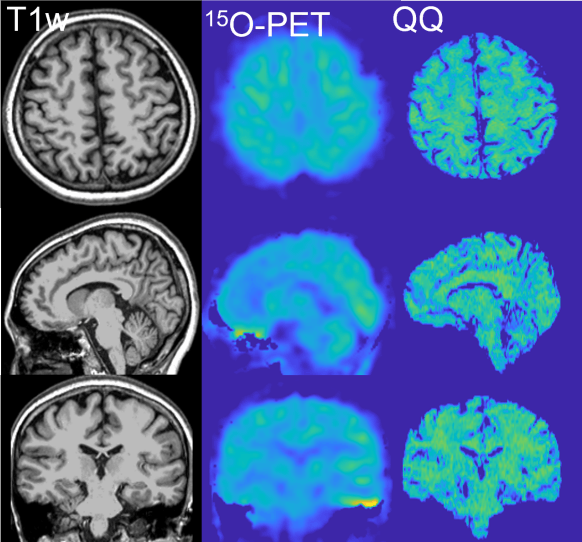

To validate our techniques, we are comparing ours with other imaging methods. For clinical application, the validation is essential to investigate the accuracy of our techniques. Our QQ provided consistent OEF values to a well-investigated MRI method, Calibrated fMRI, and the reference standard 15O-PET in healthy subjects.

See our recent work on comparison with Calibrated fMRI and 15O-PET